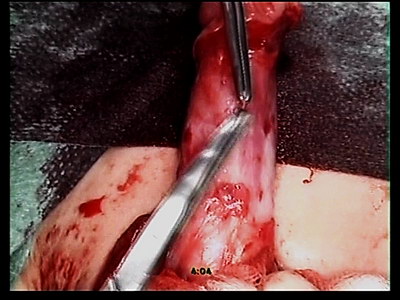

Выполнен разрез на головке и венечной борозде окаймляя наружной

отверстие. Дистальный отдел уретры с диспластическими изменениями,

истончен. Измененная зона уретры резецирована. Мочеиспускательный

канал сформирован по методу Дюплея, непрерывными узловыми

швами, головка ушита двумя рядами швов. Мясистая оболочка